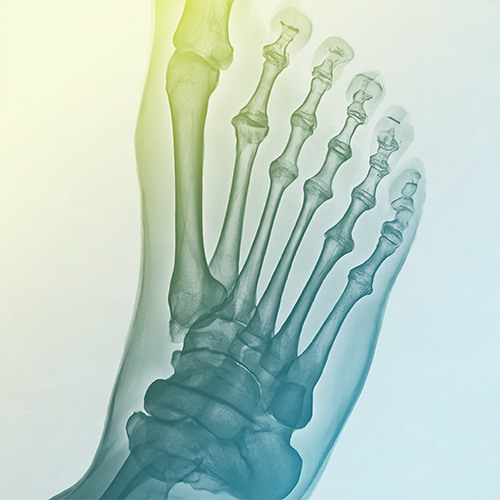

Foot Surgery

Addresses complex foot structure issues (26 bones, 33 joints). Treats deformities affecting feet and toes to maintain stability and movement for daily activities.